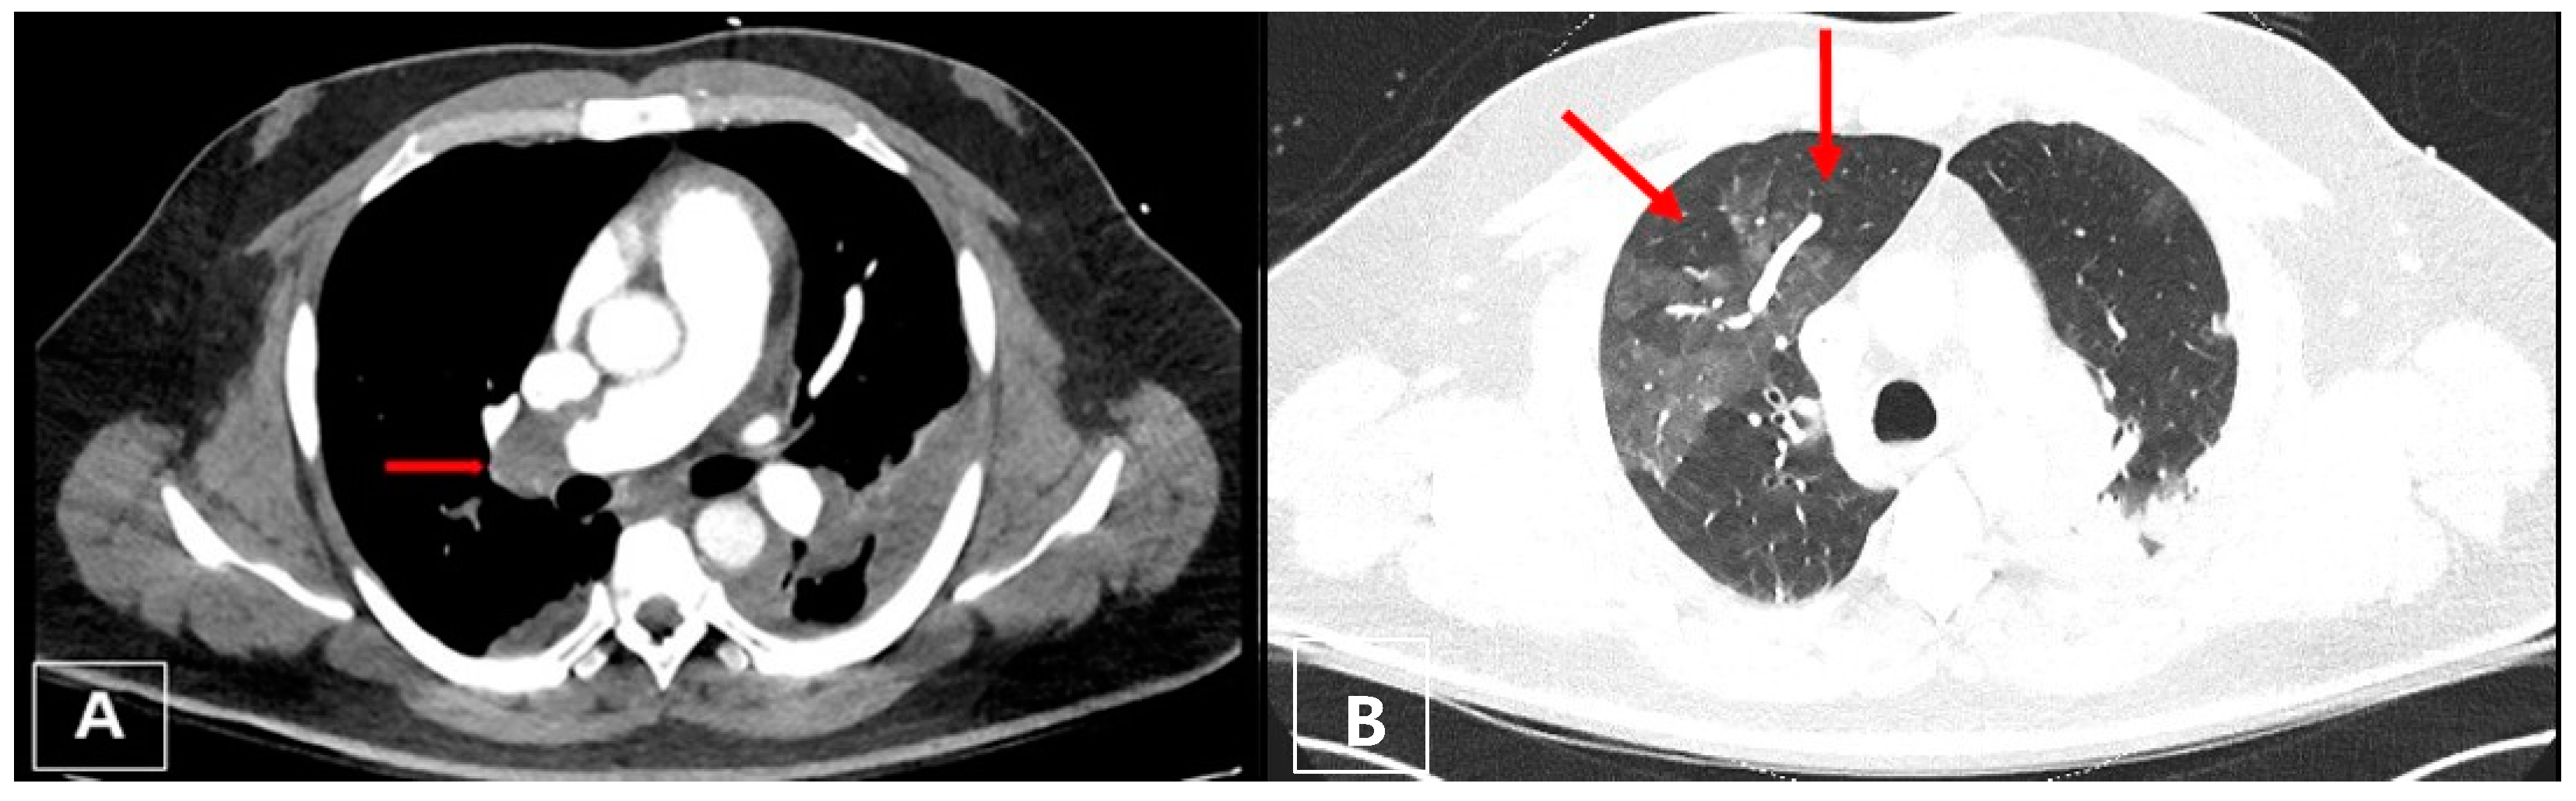

3.3. Imaging

3.4. Computed Tomography Pulmonary Angiography (CTPA)